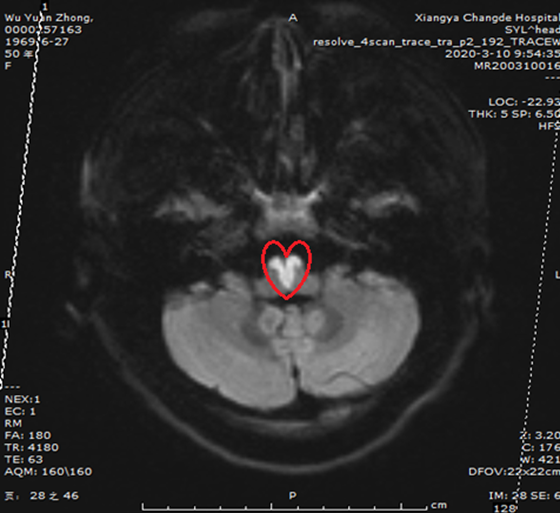

近日,来自张家界的吴女士突发脑梗死被湘雅常德医院神经内科收治入院。经脑部磁共振检查,图像上竟呈现出一个完美的“爱心”形,这便是导致吴女士四肢瘫痪,言语不能的罪魁祸首!

在进一步的头颅磁共振检查中,印证了周文斌教授最初的猜测,图像上赫然出现的“心形图案”,即脑梗死中罕见的双侧延髓内侧梗死。

据周文斌主任介绍,延髓内侧梗死是一种少见的缺血性脑血管疾病,单侧延髓内侧梗死的发病仅占所有卒中的0.5%-1.5%,而双侧延髓内侧梗死在临床上则更为罕见,国内报道的发病人数也仅有30例左右。该病早期临床症状并不典型,部分可表现为恶心、呕吐等消化道症状,主要表现为四肢瘫、延髓麻痹、双侧深感觉障碍,伴或不伴舌瘫,严重者出现呼吸困难。因此临床上非常容易误诊为食物中毒、Guillain–Barre综合症、重症肌无力和脑干脑炎等疾病。吴女士体型肥胖,有高血压病史未予重视,早期出现恶心、呕吐症状时误以为是肠胃问题而错过了最佳的溶栓治疗时机。